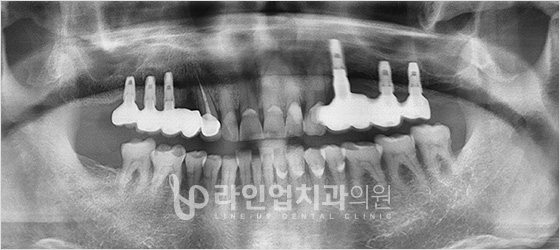

Имплантация всех зубов

Протезы на имплантах